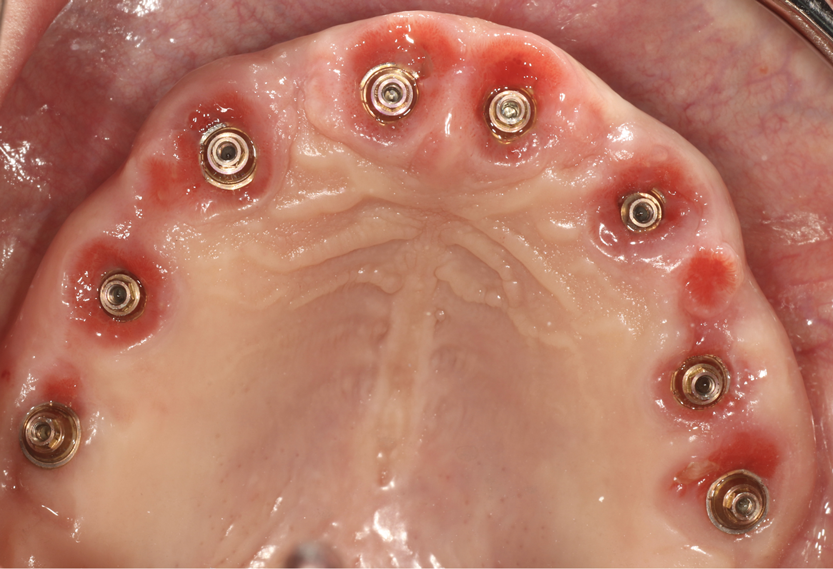

A 66-year-old male patient presented to the clinic with failing maxillary dentition. Along with a plan to address the extensive decay and tooth mobility, the patient expressed a desire for a cosmetic outcome. Treatment options included extractions with implant placement, extractions with removable prostheses, and periodontal maintenance with a guarded long-term prognosis. The patient elected to undergo extraction of his maxillary teeth, with implant placement and a fixed full-arch prosthesis (All-on-X).

An All-on-X treatment approach for a patient requiring full-arch rehabilitation involves a number of considerations with regard to fixed restorative options. Fixed restorative options include FP1 - tooth replacement only; FP2 - tooth elongated or slight pink replacement; and FP3 - tooth and tissue replacement.21 FP3 requires significant bone reduction to create the restorative space required to simulate both tooth and tissues. While FP3 is easier to accomplish, the amount of bone reduction required would potentially jeopardize the esthetic outcomes desired by the patient. FP1 may allow a better esthetic appearance, but the results can be difficult to achieve; without controlling the amount of bone reduction required for restorative space, the outcome may head from an FP1 to an FP2/3. Utilizing the advanced tools of the CS MAR along with IOS and facial scanning using CS 9600 (Carestream Dental; alternatively: RAYSCAN Studio, Ray America; Viso® G7, Planmeca) (Figure 13), a proper 3D simulation was created and a plan for the full-arch rehabilitation was developed. For this patient, the plan included incorporating partial extraction therapy for buccal plate preservation and fabrication of a scalloping guide to control the restorative and esthetic space.

A stackable metallic guide22 (Figure 14) (Chrome GuideSmile, Chrome; alternatively: stackable non-metallic guide, Surgical Guide and Start Bit, NDX nSequence; stackable non-metallic guide, Anatomic Guide, 3Sixty) was created through the use of planning software (Blue Sky Plan®, BlueSkyBio; alternatively: R2GATE®, MegaGEN; RealGUIDE Plan, RealGUIDE). A pin installation guide that seats over the existing teeth was used to install a foundational base for which the remaining stackable guides could be attached. The attachments seat and lock by means of a Swiss locking mechanism. After PET was performed and the remaining root sections were shaped and cleaned, a scalloping guide was inserted to aid in hard tissue sculpting. This sculpting is predetermined by the heights of contour of the prefabricated provisionals incorporating desired emergence profiles. Surgical guidance of subsequent drills and implants (AnyRidge; alternatively: Neodent® Grand Morse, Straumann; NobelReplace®, Nobel Biocare) was delivered using the osteotomy guide. Multi-unit abutments were inserted to create passivity and path of insertion. Temporary cylinders were attached, and the prefabricated metal-

reinforced provisional (Figure 15) was luted in the mouth with intraoral pick-up material, creating a screw-retained provisional appliance (Fig-

ure 16). The provisional was removed, and flowable composite was added to the intaglio to help guide and shape the tissue for proper emergence profiles. Gap grafting was completed, and the provisional was reinserted. The patient was given proper postoperative instructions, including dietary plans to eat soft foods only. The surgery was unremarkable, and the postoperative results were as predicted.

Three months postoperatively, the patient was recalled for a follow-up visit. The soft and hard tissues were preserved (Figure 17), and the patient reported that he was extremely pleased with the current provisional. Final extensive digital impressions were taken. Photogrammetry23,24 was used to capture implant position via domino-like scan flags. A fit verification jig (iJIG, Roe Dental; alternatively: verification jig, Absolute Dental Services; verification jig, Technique Porcelain Studios) scan25  of the provisionals with scan analogs attached was obtained to capture the shape of the provisionals related to implant position (Figure 18). To capture the soft tissue, IOS using scan bodies was incorporated. This imperative scan will show any discrepancies or gaps between the provisional and soft tissue. The opposing intraoral scan and occlusion were captured as well.

A final prosthesis was created using CAD/CAM software (Exocad software, Exocad; alternatively: 3Shape Design Studio, 3Shape; Medit Design, Medit)  (Figure 19). After analyzing and adding changes to the incisal edges virtually, the final full monolithic zirconia prosthesis was milled. At the insertion visit, no adjustments were required. At the 3 year follow-up visit, excellent maintenance of hard and soft tissues was observed, and the patient reported that he was extremely satisfied with the results (Figure 20).